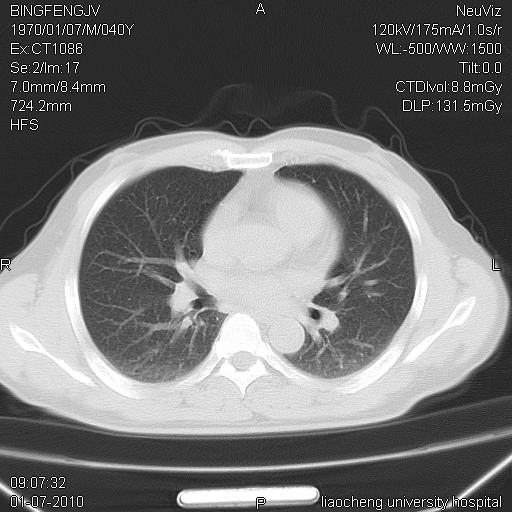

标题: CT23764B:男 40 肺部CT [打印本页]

标题: CT23764B:男 40 肺部CT

治疗2周后

考虑左肺上叶近胸膜下炎症并肺气囊形成。

炎症,大部吸收。